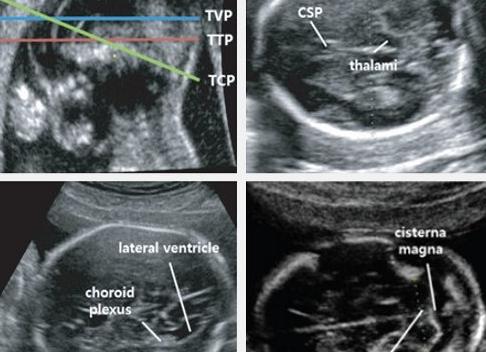

Измерение размеров головки проводится при строго поперечном УЗ-сканировании на уровне определенных анатомических структур головного мозга (полости прозрачной перегородки, ножек мозга и зрительных бугров), как показано в правой части рисунка 1.

Рисунок 1 – Схема измерения размеров головки плода

1 – полость прозрачной перегородки, 2 – зрительные бугры и ножки мозга,bd– бипариетальный размер,ac– лобно-затылочный размер

Изучение структур головного мозга начинается еще при измерении размеров головы, ведь при внимательном рассмотрении врач может определить целостность костной структуры, наличие экстракраниальных (снаружи от черепа) и интракраниальных (внутричерепных) образований. Проводится исследование больших полушарий головного мозга, боковых желудочков, мозжечка, большой цистерны, зрительных бугров и полости прозрачной перегородки. Ширина боковых желудочков и переднезадний размер большой цистерны – в норме не превышает 10 мм. Увеличение этого показателя говорит о нарушении оттока или выработки жидкости и появлении гидроцефалии – водянки головного мозга.